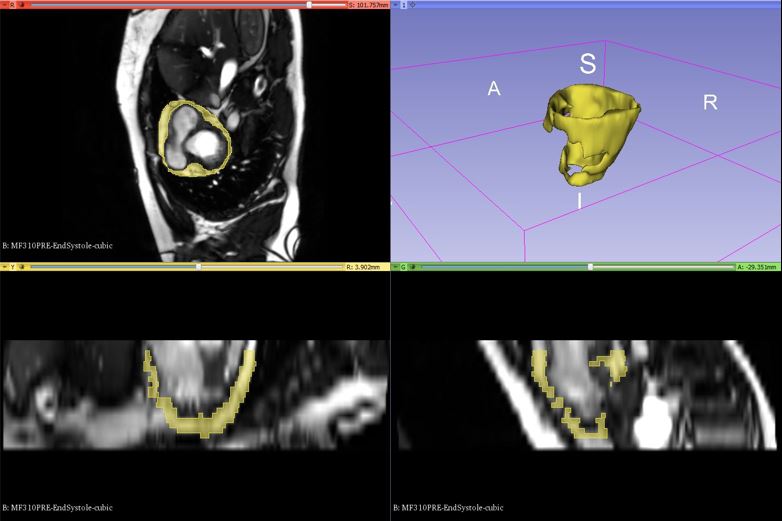

Obesity is a wide-ranging health problem and fat depots around the heart have been linked to the risk of cardiovascular disease. Magnetic Resonance Imaging (MRI) has emerged as the standard for quantifying epicardial fat for clinical studies but requires the analysis of a large number of images in a short time. We work on 3D segmentation of epicardial adipose tissue (EAT) and the development of tools to aid in studies of EAT and its relationship to cardiovascular disease and risk.